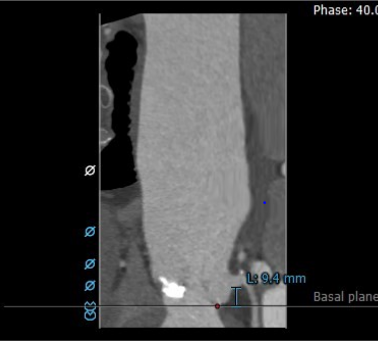

TAVR CT:瓣环平面,左室流出道(瓣下5mm)

TAVR CT:左右冠高度

1.功能性二叶瓣,右无冠窦融合,重度钙化,左窦小,LCA开口高度9.4mm,极度横位心,心脏角度103°;

3.钙化团块距离左冠脉较近,存在左冠脉风险;